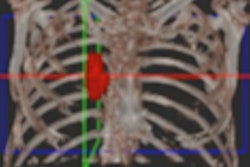

A 65-year-old man with severe lung emphysema (light blue on images below) seen on axial CT image (image 1 above), CT image including AI-based calculation (image 2), and 3D model (image 3). Extent of low-attenuation volume is seen inside green outline in both lungs in image 2. Purple outline in anterior right part of image 2 marks boundary between upper and middle lobes. Gray outline in image 2 correctly segments lower part of upper lobe and ensures that all lung tissue was considered. Also in image 2, orange outline denotes margin of tracheobronchial tree, and blue outline denotes margin of left lower lobe. All images courtesy of the AJR.The results indicate that AI-based emphysema quantification meaningfully reflects clinical pulmonary physiology, according to the researchers.